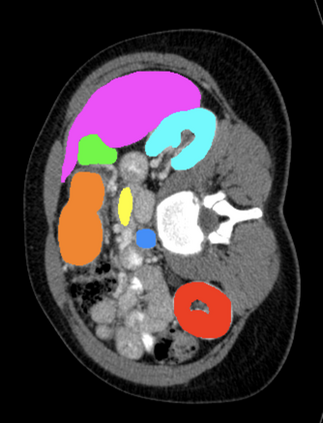

Most recent semantic segmentation methods adopt a U-Net framework with an encoder-decoder architecture. It is still challenging for U-Net with a simple skip connection scheme to model the global multi-scale context: 1) Not each skip connection setting is effective due to the issue of incompatible feature sets of encoder and decoder stage, even some skip connection negatively influence the segmentation performance; 2) The original U-Net is worse than the one without any skip connection on some datasets. Based on our findings, we propose a new segmentation framework, named UCTransNet (with a proposed CTrans module in U-Net), from the channel perspective with attention mechanism. Specifically, the CTrans module is an alternate of the U-Net skip connections, which consists of a sub-module to conduct the multi-scale Channel Cross fusion with Transformer (named CCT) and a sub-module Channel-wise Cross-Attention (named CCA) to guide the fused multi-scale channel-wise information to effectively connect to the decoder features for eliminating the ambiguity. Hence, the proposed connection consisting of the CCT and CCA is able to replace the original skip connection to solve the semantic gaps for an accurate automatic medical image segmentation. The experimental results suggest that our UCTransNet produces more precise segmentation performance and achieves consistent improvements over the state-of-the-art for semantic segmentation across different datasets and conventional architectures involving transformer or U-shaped framework. Code: https://github.com/McGregorWwww/UCTransNet.